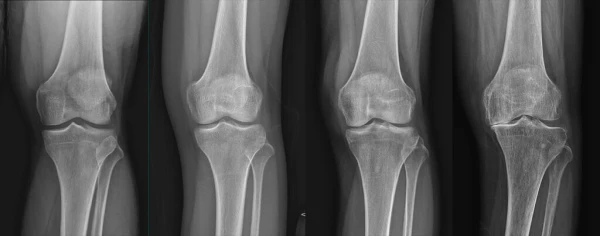

통풍은 주로 체내에 과다 축적된 요산으로 인해 발생합니다. 요산은 우리가 섭취하는 다양한 음식이 소화되어 최종적으로 대사된 후 혈액에 녹아 있다가 소변으로 배출되는 물질입니다. 일반적으로 혈액 내에서 요산은 정상 수준을 유지하며 배설됩니다. 그러나 통풍 환자는 혈액 내 요산이 과다하게 증가합니다. 이러한 과다 축적된 요산은 결정체로 변화하고, 이러한 결정체가 관절 내에 침착하여 염증을 일으킵니다.

통풍 환자는 대개 고요산혈증이라 불리는 혈액 내 요산이 정상치를 넘어선 상태를 가지고 있습니다. 그러나 고요산혈증이 있더라도 모든 고요산혈증 환자가 통풍 환자는 아니며, 무증상으로 고요산혈증인 사람이 더 많습니다. 통풍 관절염은 고요산혈증이 심하고 지속되는 경우에 발병할 가능성이 크며, 발병 확률은 기간이 길수록 높아집니다.

통풍을 적절히 치료하지 않을 경우, 발작성 관절염의 빈도가 증가하고 침범하는 관절 수도 더 많아지며, 회복에 필요한 시간도 증가합니다. 반복적인 관절염은 관절을 점차 손상시키며, 만성적인 관절염으로 진행될 수 있습니다. 또한 통풍성 결절이라 불리는 덩어리가 관절 주위나 피부 조직에 나타날 수 있습니다. 이러한 결절은 요산 결정체의 덩어리로 어느 부분에서든 형성될 수 있으며, 주로 팔꿈치, 귀, 손가락, 발가락, 발목 등에서 발생할 수 있습니다. 때로는 요로 결석을 형성하기도 합니다.

1) 한 군데 관절(엄지발가락, 발목, 무릎 등)이 갑자기 붓고 빨갛게 변하며, 손을 움켜쥘 수 없을 정도로 심한 통증이 발생합니다.

4) 엄지발가락 관절에 염증이 잘 발생하는 것이 특징이며, 무릎, 발, 발목, 손목, 팔꿈치 등 다른 관절에서도 발생할 수 있습니다.